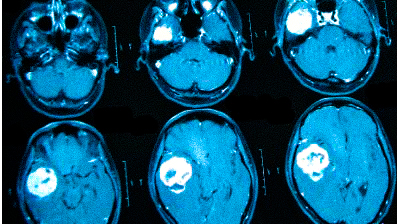

МРТ головного мозга. Обработка изображения в объеме и цвете.

Обязательно. Головные боли связаны с разными причинами. МРТ головного мозга позволяет исключить самые опасные из них – опухоли, поражение сосудов (аневризмы, мальформации и т.д.), «водянку» мозга (гидроцефалия) и т.д. Часто головные боли связаны с воспалением в придаточных пазухах носа, что также хорошо видно при МРТ. Если при МРТ не нашли патологии мозга, это очень хорошо. Разумеется, обследование даёт информацию о патологиях, но не всегда даёт ответ на вопрос «почему болит голова?». Головные боли имеют сложное происхождение. Ваш невролог будет подбирать лекарство, которое вам обязательно поможет.

Головные боли одна из наиболее частых жалоб, с которой обращаются пациенты к невропатологам, а также для углубленного обследования. Известно много причин головных болей, среди которых можно выделить «органические», то есть те которые можно увидеть, и функциональные. К «органическим» причинам головных болей можно отнести опухоли, гидроцефалию («водянку», избыточное количество жидкости в головном мозге), патологию сосудов (аневризмы, мальформации, спазмы, кровоизлияния), воспаления придаточных пазух носа (синуситы), воспалительные процессы мозга и его оболочек (церебрит, энцефалит) и некоторые врожденные аномалии мозга. Зачастую причину головных болей непосредственно увидеть невозможно. Тогда причину головных болей можно искать по косвенным признакам. Так, остеохондроз шейного отдела позвоночника вызывает напряжение мышц шеи и затылочной области, что обозначается как «боли напряжения», напряжение глазодвигательных мышц также часто вызывает боли в глазах и голове.

Очень часто при МРТ головного мозга, особенно, в пожилом возрасте встречаются признаки «дисциркуляторной энцефалопатии». Этот термин и клинический, и диагностический. Он отражает «старение» мозга в условиях недостаточности общей кровообращения. Совсем необязательно, что у таких пациентов обнаружатся бывшие инсульты, хотя мелкие («лакунарные») все же иногда встречаются. Дисциркуляторная энцефалопатия проявляется при МРТ в виде единичных или множественных мелких очагов лейкоарайоза (термин предложен в 70-е годы для обозначения мелких участков глиоза, то есть распада белого вещества мозга), той или иной степени атрофии, часто гидроцефалии. Гидроцефалия может быть с лейкомаляцией – изменениями белого вещества мозга вокруг желудочков, отражающее его распад, нарушение ликврообращения и замену нормального вещества мозга глиозной тканью (своего рода «рубцом»).

МРТ при головных болях (в трех проекциях): специальная программа выстраивает объемные изображения полученных срезов, что позволяет увидеть даже мельчайшие изменения и отдифференцировать патологию от нормы